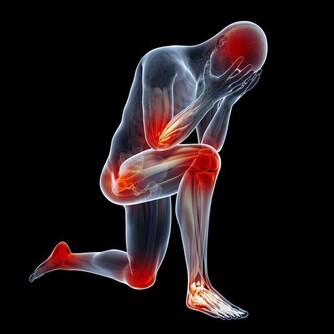

糖尿病屬於一種代謝性疾病,目前對於它並沒有治癒的方法,只能依靠藥物和飲食來控制,因此對於糖尿病要及早防治。糖尿病在早期會出現一些症狀,大家可以了解一下,以便及時發現和控制,且更好的防止並發症的發生。下面來看看糖尿病的六大標誌表現。

6、傷口難癒合

糖尿病的發生會阻礙血液流通,從而可導致傷口癒合時間延遲,甚至還可損傷神經組織。因為皮膚的傷口癒合需要充分的血液流通,否則會降低治愈能力,如發現有傷口血流不止等異常現象的,建議要及時到醫院接受診斷。